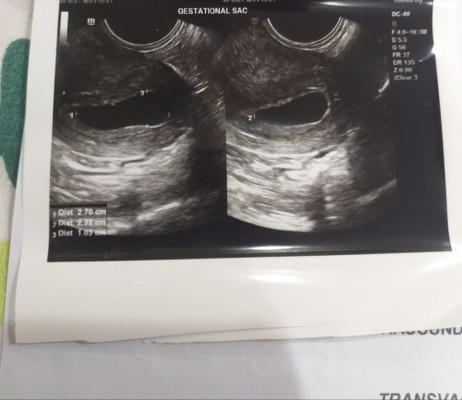

empty gestational sac

hello po cno po same situation sakin empty gestational sac. via trans v po ang age 6 weeks and 5 days. lmp ko po is may 16..dapat 8 weeks nako now. sana may hope pa makita baby ko! 😔 #pleasehelp #advicepls #FTM #firsttimemom #respect_post